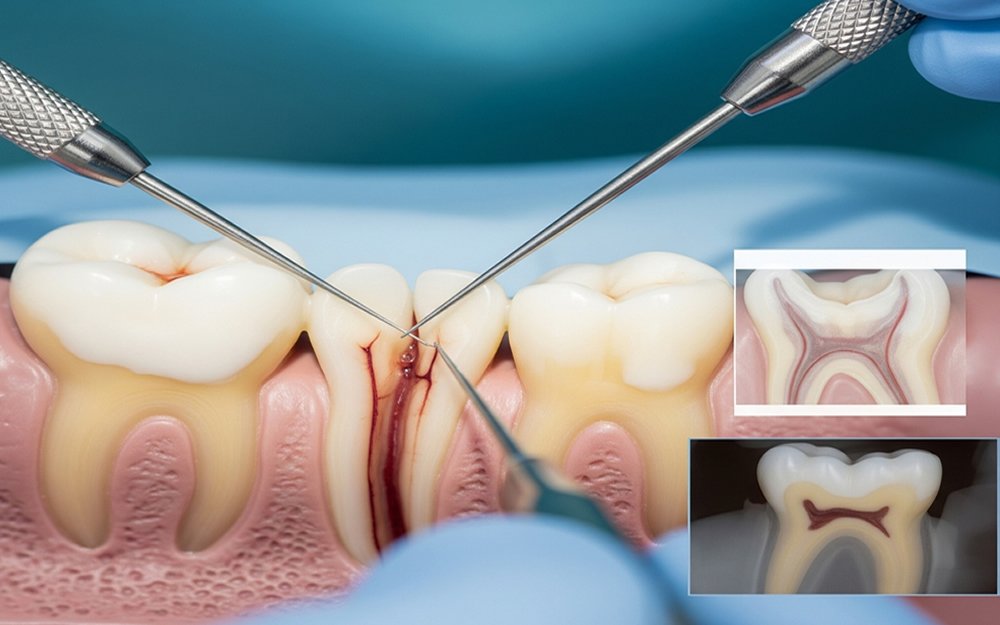

Inside every tooth is a soft tissue called pulp. This pulp contains nerves and blood vessels. When the pulp becomes infected due to deep cavities, cracks, trauma, or repeated dental procedures, pain and infection start developing. If ignored, the infection canany spread to the jawbone and surrounding tissues.

Root canal treatment removes the infected pulp, cleans the canals, and seals the tooth, stopping pain and preventing further infection.

Removal of Infected Pulp

The infected pulp tissue is carefully removed from the tooth. This step immediately relieves pain and pressure.

Cleaning and Shaping of Root Canals

The canals are cleaned, disinfected, and shaped using advanced rotary instruments to remove bacteria thoroughly.

Sealing the Tooth